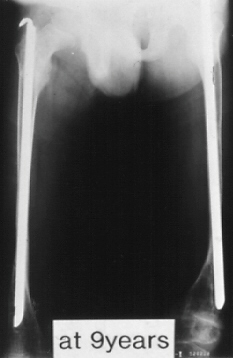

This 9 year old boy presented with the diagnosis of osteogenesis imperfecta. By age nine he sustained 16 fractures in his lower extremities and 30 fractures in his upper extremities. He started walking at 18 months of age. He now complains of pain in the ankle. At this time he is a household and minimal community ambulator. Following this fracture he did not walk and presented at age 18 with these x-rays. The diameter of the right and left femur at the age of 18 years were 7 and 8 mm's respectively.